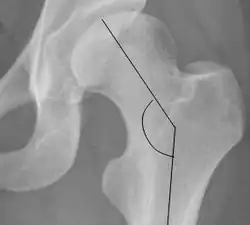

Measurements

The most useful lines and angles that can be drawn in the pediatric pelvis assessing hip dysplasia are as follows:[3]

- (A) Hilgenreiner line, connects the inferior tips of the iliac bones,[4] at the triradiate cartilage. This line is used to measure the acetabular angle and as a reference for Perkin line.

- (B) Perkin line is perpendicular to Hilgenreiner line, touching the lateral margin of the acetabular roof.[5] This leads to four quadrants and a normal femoral head has to be located in the inferomedial quadrant. We can measure the lateral displacement of the femoral head with regard to the Perkin line by dividing the width of the head that crosses the Perkin line by the diameter of the head. The value for patients under 3 years must be 0 and in older children this ranges from 0 to 22%.

- (C) Shenton line is a continuous arc drawn from the inner edge of the femoral neck to the superior margin of the obturator foramen. In children over about 3 to 4 years of age, this line should be smooth and undisrupted, otherwise it may indicate a fracture or hip dysplasia.[6] However, in infants this line can be unreliable as it depends on the rotation of the hip when the image is taken.[7]

- (D) The acetabular index measures the acetabular roof slope. It is the most useful measure of acetabular dysplasia until 6 years of age. It is formed between Hilgenreiner line and the acetabular roof. In newborns, values of in males and in females are considered normal. It normally decreases with age:

- (E) The medial articular joint space is measured between the medial border of the femoral head or neck (when epiphysis is not ossified) and the acetabular platform. Normal values range between 5 and 12 mm. Differences greater than 1.5 mm between the two sides are considered abnormal.

- Reimer's migration index (MI), also called the femoral extrusion index,[3] is calculated if hip dysplasia is detected. It can be used to indicate hip dislocation. It is the horizontal distance (parallel to the Hilgenreiner Line) between the Perkin line and the lateral border of the ossification center of the femoral head, divided by the horizontal width of the ossification center. The migration index is normally less than 33% by most sources,[9] but 25% and 30% has also been suggested.[10]